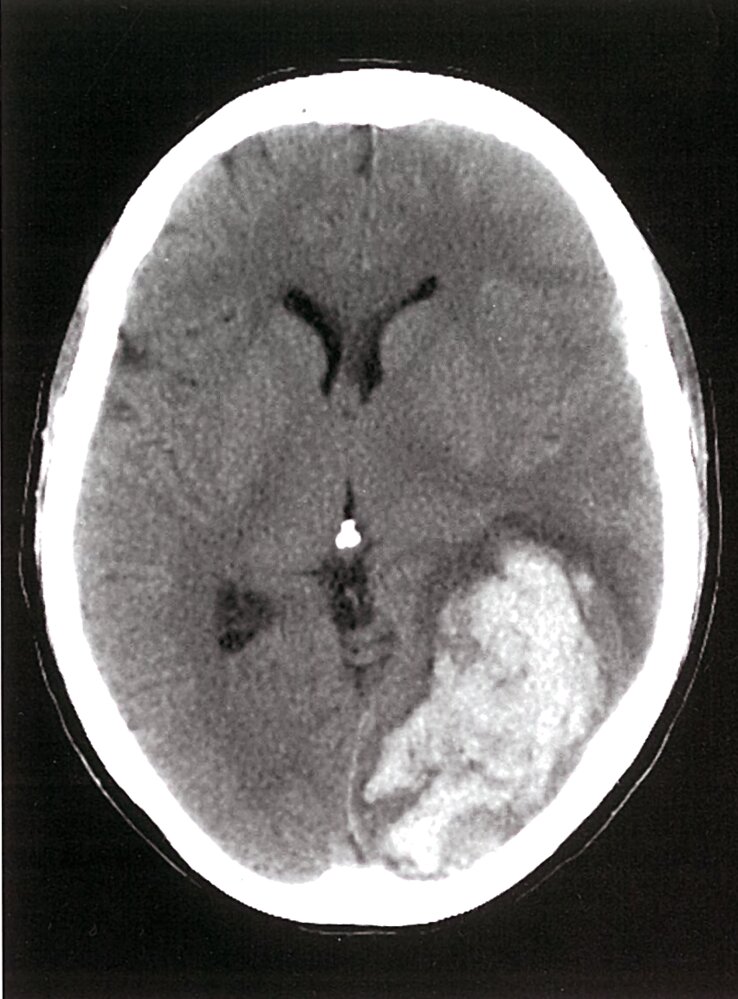

Neuroimaging: e.g., CT head

- Consider immediate neurology and/or neurosurgery consult for suspected acute stroke, intracranial bleed, or cerebral herniation.

Stroke (hemorrhagic or ischemic)